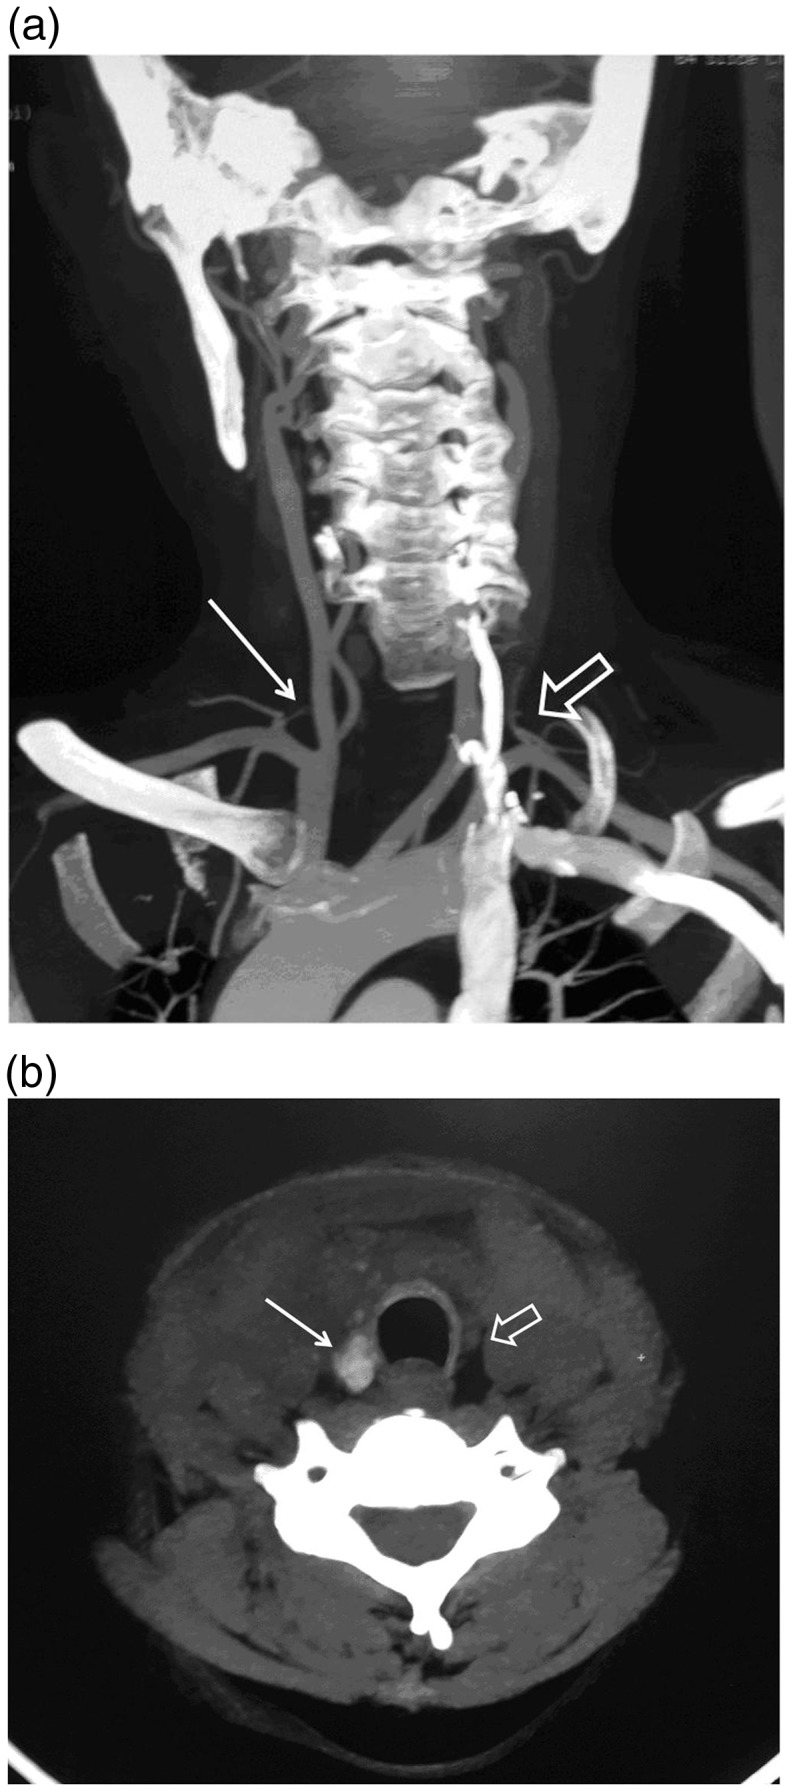

Thyroid hemiagenesis is a rare form of thyroid dysgenesis characterized by an absence of half of the thyroid gland. Developmental hemi-thyroid anomalies can result from either an abnormal descent or an agenesis of one lobe of the thyroid gland. We report a case of a 40-year-old woman with history of a longstanding gradually progressive thyroid swelling without any complication. An ultrasonographic examination diagnosed the absence of the left thyroid lobe and enlargement of the right lobe, which was confirmed on a computed tomography (CT) angiogram and a radionuclide scan of the neck. A cytological examination showed nodular goiter with cystic degeneration. Right subtotal thyroidectomy was performed and histopathological examination confirmed adenomatous goiter with degenerative changes. We report the rarity of the condition and emphasize the role of a comprehensive radiological, cytological, and radionuclide algorithm for an accurate preoperative diagnosis and subsequent management.